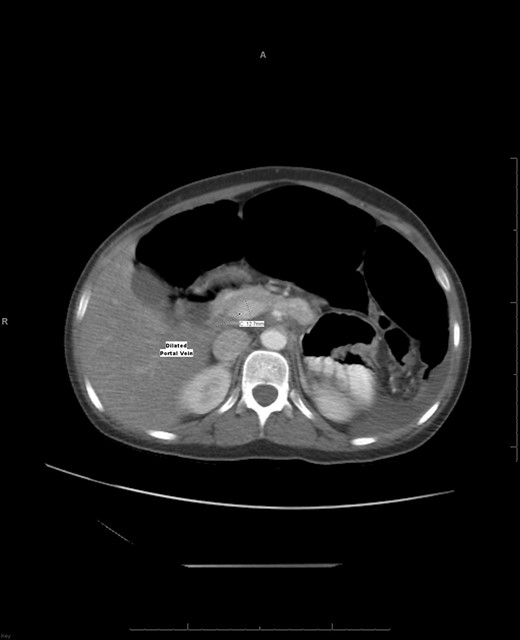

Laboratory investigation showed a white blood cell count of 15.13 × 103/UL, (mainly neutrophilia of 90.3%), a hemoglobin level of 9.4 g/dL, and a platelet count of 189 × 103/UL. The other biochemical parameters including liver enzymes were normal apart from a trace of jaundice, with total Bilirubin of 2.43 mg/dL and direct Bilirubin of 0.45 mg/dL. Chest X-ray showed bowel loops at the splenic fossa (Fig. 1). An initial diagnosis of a torted ovarian cyst was made. A pelvi-abdominal ultrasound revealed normal adnexa but a right-sided soft pelvic-abdominal mass with the absence of a splenic shadow at the left hypochondrium. Subsequently, CT scan of the abdomen and pelvis revealed a large right-sided infarcted spleen of 30 × 16 × 10 cm3 (Fig. 2) and a ‘whirl sign’ of the splenic pedicle (Fig. 3). Furthermore, CT scan showed signs of portal hypertension (Fig. 4) associated with mesenteric varices (Fig. 5). The patient subsequently underwent a surgical exploration.

An axial CT shows a widening portal vein 12.7 mm in diameter indicating portal hypertension with multiple dilated portal veins seen at the liver parenchyma.